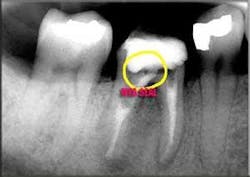

Endodontic therapy is no exception. The goal of root-canal therapy is to treat pulpal bacterial infection through removing infected tissues and then effectively sealing the tooth to prevent re-infection (see figures 1 (left) and 2 (right)). The more thorough and careful the therapy, the more efficient it becomes. Careful diagnosis and cleaning of the tooth, for example, improves the long-term success rate of endodontic procedures and, at the same time, reduces the chances that they will have to be re-done. In addition, immediate efficiencies can also be realized by properly approaching and executing endodontic procedures.

Therefore, understanding the extent of the infection, along with the overall structural soundness of the tooth, is critical to ensuring the procedure will be both efficient and successful. I utilize extraoral and intraoral X-rays and illuminated magnification; these allow me to potentially visualize calcification, cracks, voids, and, occasionally, pulp stones (see figure 3, above). That said, canals are infrequently as straight as they may appear on a radiograph. They tend to be oval and irregular rather than round and regular, and typically present with a variety of curvatures, including bayonet shapes (see figure 4, below).